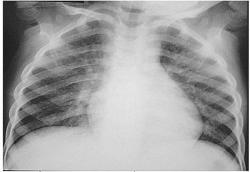

Viêm đường hô hấp

![]() |

| Khi thời tiết chuyển mùa, trẻ dễ mắc các bệnh viêm đường hô hấp. |

Khi thời tiết bắt đầu chuyển mùa, các loại vi rút dễ dàng xâm nhập vào cơ thể trẻ và phá vỡ hệ thống đề kháng chưa hoàn chỉnh của trẻ, nhất là hệ hô hấp làm cho trẻ bị viêm phế quản, viêm đường hô hấp, viêm phổi.

Bệnh lây truyền qua đường miệng, nước bọt, tiếp xúc tay và các đồ dùng để ăn uống. Trẻ có thể sốt cao đột ngột, đau đầu, lạnh, đau toàn thân; đau họng, ho, mệt mỏi; chán ăn, khó thở, tiêu chảy nhẹ...